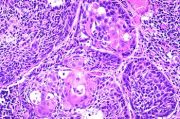

| 2021年12月10日 (五) 13:16 | 16号切片-鳞癌(癌巢)-镜下观2.jpg (文件) |  |

62 KB | Cirno.9 | 基于MsUpload的文件上传 | 1 |

| 2021年12月10日 (五) 13:16 | 16号切片-鳞癌(癌巢)-镜下观1.jpg (文件) |  |

180 KB | Cirno.9 | 基于MsUpload的文件上传 | 1 |

| 2021年12月10日 (五) 13:17 | 16号切片-鳞癌-镜下观2.jpg (文件) |  |

50 KB | Cirno.9 | 基于MsUpload的文件上传 | 1 |

| 2021年12月10日 (五) 13:17 | 16号切片-鳞癌-镜下观1 .jpg (文件) |  |

50 KB | Cirno.9 | 基于MsUpload的文件上传 | 1 |